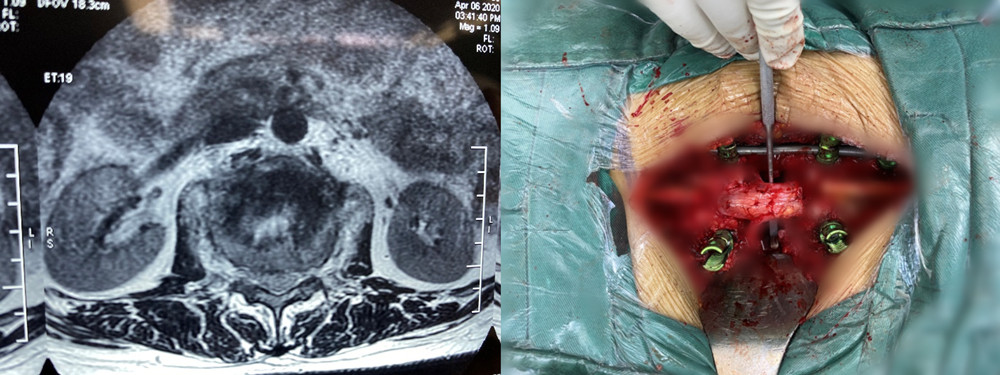

该患者家庭经济拮据,且疫情期间无法外请北京专家前来手术,患者及家属辗转自治区多家医院找到赵岩医生,赵岩团队经过反复讨论和充分准备,最终在麻醉科(手术室)紧密配合下独立完成一期后路固定+En-bloc腰1椎体肿瘤切除术+椎体重建术,该手术首先行后路脊柱固定,其次从后方经椎弓根将病变节段的后部结构整块切除,再向前方分离骨膜和椎体周围血管(这是手术风险最大的步骤),分离彻底后将椎体一并整块切除,最后重建脊柱前中柱。

脊柱截骨手术分六级,此手术属五级截骨手术(VCR),是单椎体最高级截骨手术。术中克服了没有介入科血管栓塞辅助支持等重重困难,最终整个手术仅耗时2个小时顺利将肿瘤椎体完整切除并行腰1椎体重建,出血量500ml。

术中